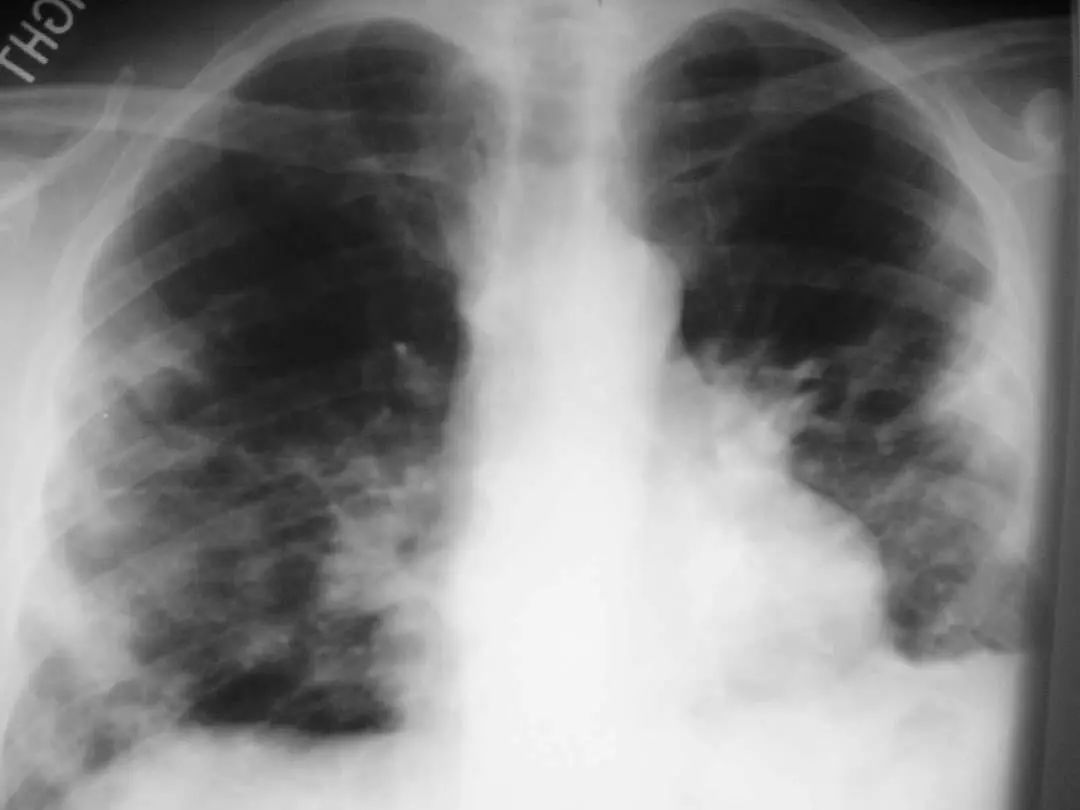

图1.10 48岁的流感嗜血杆菌性肺炎患者, 胸部X线片显示双侧不透明,主要分布在外周。